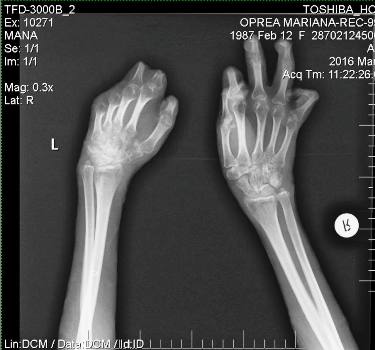

novalue Mariana, membru fondator al Asociaţiei Colectiv GTG 3010, a publicat si o radiografie a mainilor sale, in care se vede ca degetele de la mana stanga sunt mai scurte decat cele de la cea dreapta. „Va trebui să continui kinetoterapia ca până acum, adică zilnic, pentru mobilitatea braţelor. Grefele s-ar strâns foarte mult, pielea s-a uscat şi nu pot întinde mâinile complet. În următoarele 2-3 luni va trebui să mă întorc pe patul de spital pentru alte intervenţii chirugicale. Mi-aş dori foarte mult să pot să am o proteză bionică pentru mâna stângă, care nu mai are niciun deget. Chiar dacă intervenţia va fi una grea şi vor trebui să îmi taie jumătate din palmă pentru a o integra, o proteză dintre cele de generaţie nouă poate prelua până la 95% din funcţiile normale ale mâinii. O proteza ajunge la 90.000 de euro”, a mai marturisit Mariana Oprea.